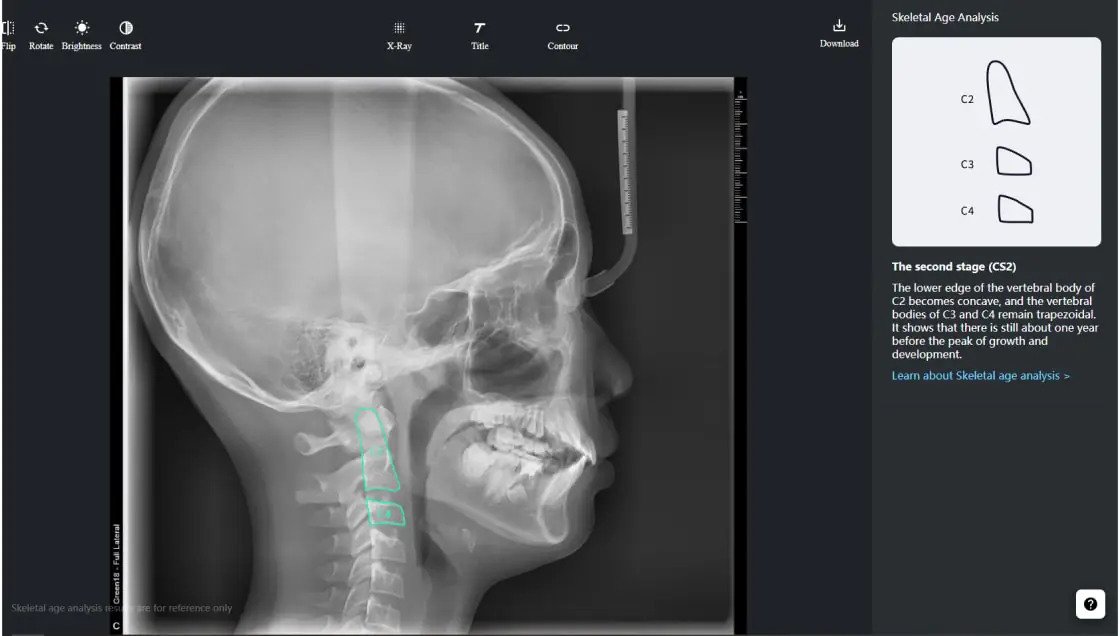

Intelligent Cephalometry System

Intelligent Cephalometry System (ICS) :

• Tracing based on AI

• Superimposition

• Skeletal age analysis based on AI